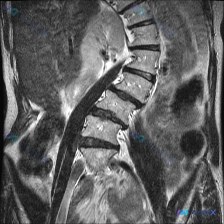

整理到一份腹部MRI的影像分析资料,有点意思——用户最初的疑问是“这张图能看到脊柱侧弯吗”,但读下来发现,真正可能需要紧急处理的问题不在脊柱,而在脾脏。 先不说结论,先放关键影像表现: 1. 肝脏、胆道、胰腺、双肾(除右肾位置稍低)未见明显重大异常; 2. 脾脏明显增大,下极到腰椎中下段,实质内弥漫...